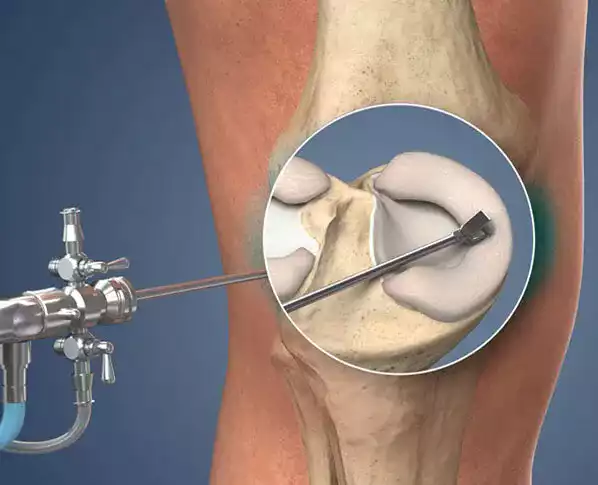

We offer a wide range of health solutions ranging from knee prosthesis and hip prosthesis to Total knee and Total hip prosthesis, from Sports surgery to Trauma surgery.

In areas such as hip prostheses, knee prostheses, anterior cruciate ligament knee arthroplasty, shoulder arthroplasty and sports surgery, Prof. Dr. Regain your freedom of movement by making an appointment with Çetin Işık .